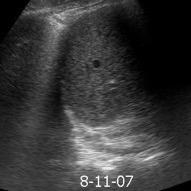

Patrón ecográfico de empiema

Anecoico.....0%. (0 de 47)

Complejo no septado no hiperecoico... ……………..0% (0 de 36)

Complejo, no septado hiperecoico......100% (2/2)

Complejo septado …35% (11 de 31)

Ecogénico homogéneo .... 100% (2 de 2)

Wang T et al. Value of ultrasonography in determining the nature of pleural effusion. Analysis of 582 cases. Medicine 2022.

Chih-Yen Tu et al. Chest Ultrasound Study Pleural Effusions in Febrile Medical ICU. Chest 2004

Yang W,et al. Infectious pleural effusion status and treatment progress. J Thorac Dis. 2017;